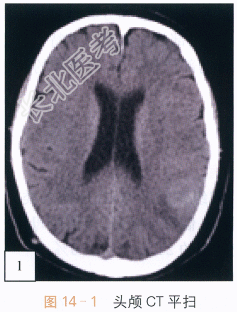

影像学资料:如图14-1~图14-4所示。

读片分析:头颅CT平扫,如图14-1所示,横断位示左颞叶见类圆形等高密度病灶,密度均匀、边界清楚,周围无明显水肿带,肿瘤临近蛛网膜下腔无增宽,脑沟脑回无受压或移位;头颅横断位MRI T₁W像,如图14-2,左颞叶类圆形低信号肿块影,内部信号稍欠均匀;邻近蛛网膜下腔无增宽,脑沟及脑回无明显受压移位;横断位T₂W像,如图14-3所示,肿块呈等高信号影,内部信号略不均匀,无明显囊变坏死及出血;增强扫描后横断位T₁W像,如图14-4所示,病灶强化稍欠均匀;病灶中必可见少许斑片状异常强化,余无明显异常强化,无脑膜尾征。